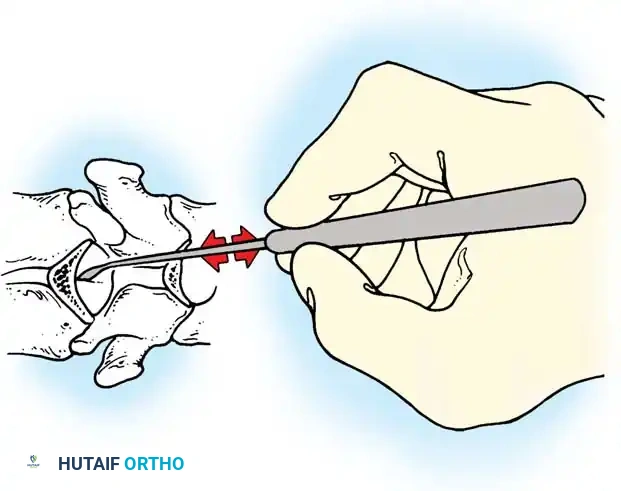

Lateral Exposure and Hemostasis

- Transverse Process Exposure: Extend the subperiosteal dissection laterally, first exposing the facet joints, and then continuing out to the tips of the transverse processes bilaterally.

- Segmental Vessels: As you dissect lateral to the facet joints, you will encounter the posterior branches of the segmental vessels. These must be meticulously identified and coagulated with bipolar or monopolar cautery to prevent insidious bleeding.

Fig. 38-24: Posterior view of segmental vessels located just lateral to each facet joint, requiring meticulous coagulation.

- Facet Cleaning: Use a sharp curet and a pituitary rongeur to completely excise the facet capsules and clean the interspinous ligaments.

Clinical Pearl: Always direct your curet from the midline laterally when cleaning the facet joints. This directional force ensures that if the instrument slips, it moves safely away from the spinal canal, preventing catastrophic dural tears or iatrogenic spinal cord injury.

Fig. 38-25: Cobb curets utilized to meticulously clean the facets of all ligamentous and capsular attachments.